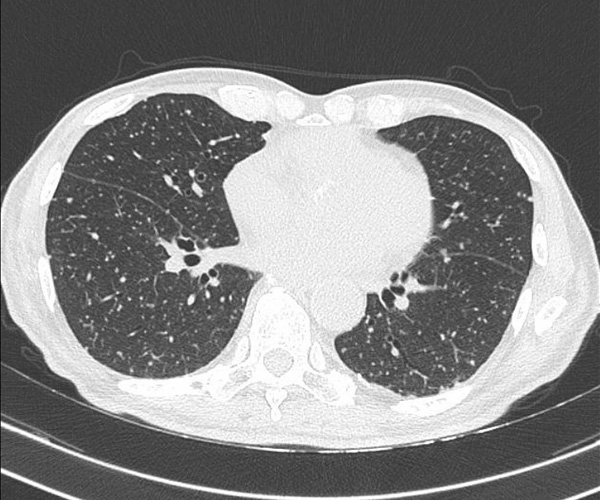

Figura 3. TC torace

Il paziente veniva successivamente sottoposto a TC torace con riscontro di un quadro compatibile con TBC miliare (Figura 3).

In alcuni pazienti con infezione disseminata da BCG, la radiografia del torace o la tomografia computerizzata (TC) mostrano un pattern nodulare o interstiziale miliare, talvolta associato ad adenopatia ilare; questi rilievi sono osservati più frequentemente in associazione con sepsi [10,45]. La sensibilità della radiografia del torace è limitata; in una serie comprendente 216 pazienti con infezione sistemica da BCG, la radiografia del torace non è riuscita a rivelare un pattern miliare in circa il 25% dei pazienti con polmonite successivamente identificata tramite TC [8].

Come nel caso del nostro paziente, si eseguono contemporaneamente colture per i micobatteri, test NAA micobatterico, colorazione Gram, coltura batterica, colorazione fungina e coltura fungina, nonché altri studi guidati dal tipo di campione (ad esempio, i pazienti con coinvolgimento articolare dovrebbero essere indagati prelevando del liquido sinoviale e valutando la conta cellulare e la colorazione dei cristalli). Inoltre, i pazienti con sintomi sistemici dovrebbero essere sottoposti a imaging del torace (tomografia computerizzata o risonanza magnetica preferita rispetto alla radiografia convenzionale) per escludere il coinvolgimento polmonare.